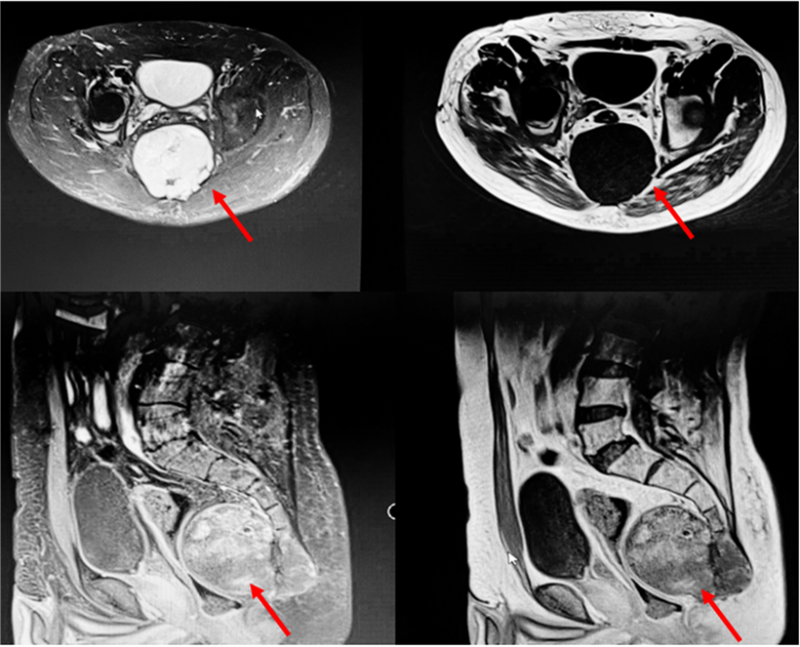

病灶巨大,达12厘米×9厘米,不仅破坏了骶骨骨质,还侵犯了臀大肌。此外,解剖位置较深,周围结构复杂,瘤体血运丰富,手术暴露困难,给切除带来了极大挑战。常黎明院长、廖光军主任团队多次在科内组织病例讨论,制定各种详尽的手术方式,包括肠道切除+直肠造瘘、皮瓣移植术等多个手术备选方案。同时运用3D打印技术,根据术前患者影像学数据,以1:1的比例3D打印骶骨模型,帮助术者更为清晰地了解和掌握肿瘤界限及侵犯程度,可以进行术前的规划和手术方案的优化,同时为患者及家属和术者提供触觉与视觉上的体验,帮助术者与患者及家属更有效地完成术前沟通。

术前,介入科帮助栓塞肿瘤滋养血管及安置腹主动脉球囊。在麻醉科、输血科保驾护航下,常黎明院长、廖光军主任团队术中利用3D打印模型,清晰明确了恶性肿瘤侵犯的软组织范围,骨破坏程度,需截骨的位置等,减少了术中X线透视的使用次数,简化了手术步骤,使术中出血量减少,复杂的骨肿瘤手术变得相对容易,最后历时3小时,出血2000毫升,顺利完成了手术。术后,王先生左侧骶3及以上神经得以保留,大小便功能未受损,刀口愈合良好。王先生对手术效果非常满意,现已顺利康复出院。